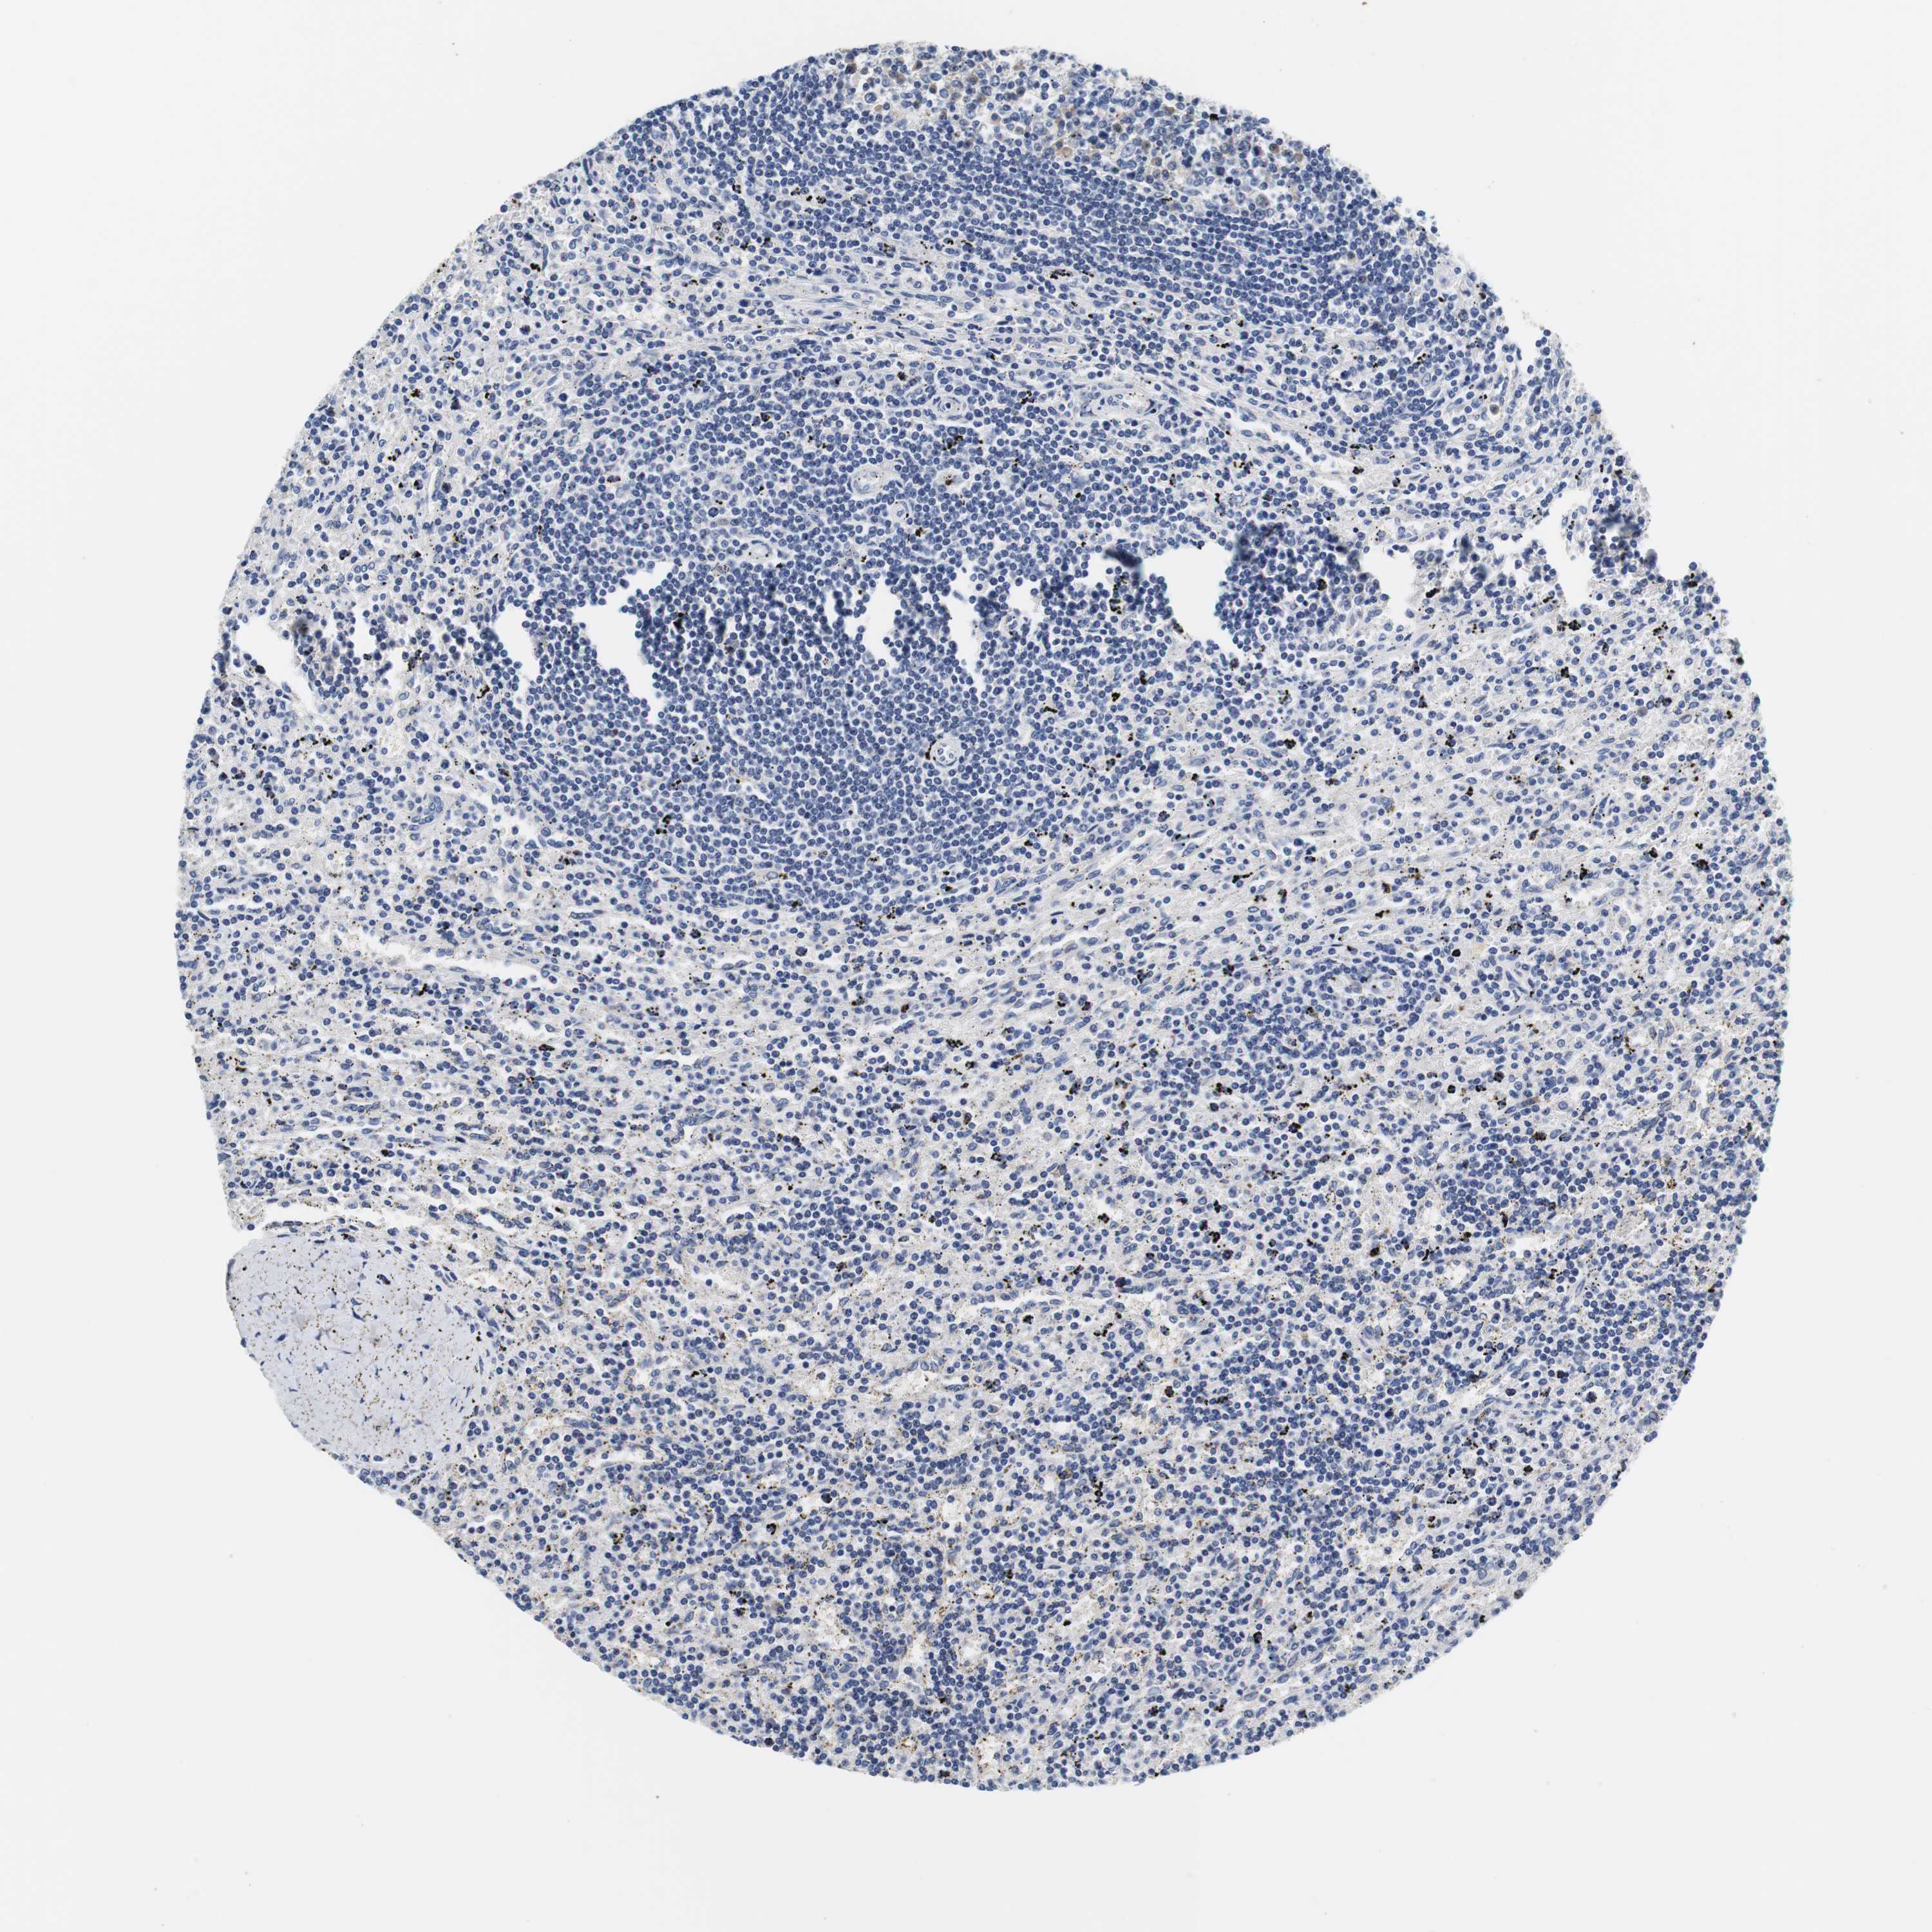

CANCER LYMPHOMA Show tissue menu

LYMPHOMA - Protein expressioni

A mouse-over function shows sample information and annotation data. Click on an image to view it in a full screen mode. Samples can be filtered based on level of antibody staining by selecting one or several of the following categories: high, medium, low and not detected. The assay and annotation is described here.

Antibody stainingi

Antibody staining in the annotated cell types in the current human tissue is reported as not detected, low, medium, or high, based on conventional immunohistochemistry profiling in selected tissues. This score is based on the combination of the staining intensity and fraction of stained cells.

Each image is clickable and will lead to virtual microscopy that enables deeper exploration of all samples and also displays staining intensity scores, fraction scores and subcellular localization as well as patient and tissue information for each sample.

Antibody HPA006277

Antibody HPA006507

Antibody CAB017027

Hodgkin's disease, NOS

Malignant lymphoma, non-Hodgkin's type, High grade

Malignant lymphoma, non-Hodgkin's type, Low grade